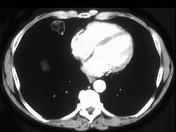

男,57岁,体检时发现肺部占位,CT检查如图,请选出最可能的诊断 ( )A.肺错构瘤B.周围型肺癌C.肺结核D.肺转移瘤E.肺曲菌病

问题 男,57岁,体检时发现肺部占位,CT检查如图,请选出最可能的诊断 ( )

选项 A.肺错构瘤 B.周围型肺癌 C.肺结核 D.肺转移瘤 E.肺曲菌病

答案 A